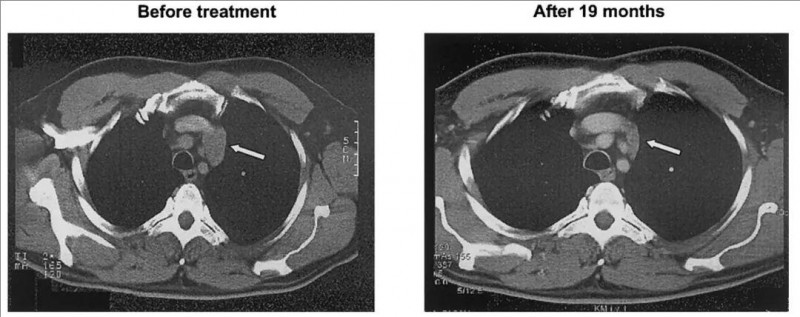

该患者确诊为滤泡中心淋巴瘤,曾接受过高剂量化疗,但效果不理想,病情仍然复发。入组接受帕米膦酸盐和低剂量IL-2,在体内刺激γδT细胞治疗后,CT检查显示,大多数淋巴结没有明显变化,且皮肤转移及纵隔淋巴结消退(详见下图)。仅有1个淋巴结增大,病理活检显示该淋巴结主要为纤维化,仅剩下少量淋巴瘤细胞。在此之后,肿瘤质量稳步下降,最终经过19个月的治疗,该患者达到部分缓解(PR)(详见下图)。

▼患者治疗前后,CT图像对比

注:CT扫描提示,患者皮肤转移及纵隔淋巴结消退(箭头)。